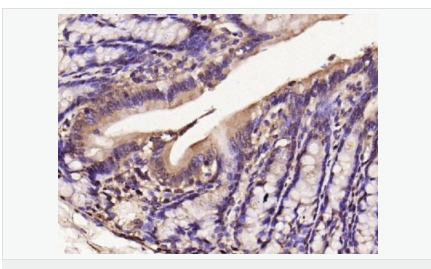

| 產品應用 | WB=1:500-2000 IHC-P=1:100-500 IHC-F=1:100-500 Flow-Cyt=1μg/Test ICC=1:100-500 IF=1:100-500 (石蠟切片需做抗原修復) not yet tested in other applications. optimal dilutions/concentrations should be determined by the end user. |

| 產品介紹 | Nitric oxide (NO) is an inorganic, gaseous free radical that carries a variety of messages between cells. Vasorelaxation, neurotransmission and cytotoxicity can all be potentiated through cellular response to NO. NO production is mediated by members of the nitric oxide synthase (NOS) family. NOS catalyzes the oxidization of L-arginine to produce L-citrulline and NO. Two constitutive isoforms, brain or neuronal NOS (b or nNOS, type I) & endothelial cell NOS (eNOS, type III), and one inducible isoform (iNOS, type II), have been cloned. All NOS isoforms contain calmodulin, nicotinamide adenine dinucleotide phosphate (NADPH), flavin adenine dinucleotide (FAD), and flavin mononucleotide (FMN) binding domains. Nitric oxide synthase is expressed in liver, macrophages, hepatocytes, synoviocytes, stimulated glial cells and smooth muscle cells. Cytokines such as interferon-gamma (IFN), tumor necrosis factor (TNF), interleukin-1 and -2, and lipopolysaccarides (LPS) cause an increase in iNOS mRNA, protein, and activity levels. Protein kinase C-stimulating agents exhibit the same effect on iNOS activity. After cytokine induction, iNOS exhibits a delayed activity response which is then followed by a significant increase in NO production over a long period of time. Human iNOS is regulated by calcium/calmodulin (in contrast with mouse NOS2). Function: Produces nitric oxide (NO) which is a messenger molecule with diverse functions throughout the body. In macrophages, NO mediates tumoricidal and bactericidal actions. Also has nitrosylase activity and mediates cysteine S-nitrosylation of cytoplasmic target proteins such COX2. Subunit: Homodimer. Binds SLC9A3R1. Tissue Specificity: Expressed in the liver, retina, bone cells and airway epithelial cells of the lung. Not expressed in the platelets. Similarity: Belongs to the NOS family. Contains 1 FAD-binding FR-type domain. Contains 1 flavodoxin-like domain. SWISS: P35228 Gene ID: 4843 Database links: Entrez Gene: 4843 Human Entrez Gene: 18126 Mouse Omim: 163730 Human SwissProt: P35228 Human SwissProt: P29477 Mouse Unigene: 709191 Human Unigene: 2893 Mouse Unigene: 10400 Rat Important Note: This product as supplied is intended for research use only, not for use in human, therapeutic or diagnostic applications. 合成與降解(Synthesis and Degradation) 催化生物體內一氧化氮(NO)生成的酶。分神經(jīng)型一氧化氮合成的酶(nNOS or NOS-1)、誘導型一氧化氮合成的酶(iNOS or NOS-2)、內皮型一氧化氮合成的酶(eNOS or NOS-3)。 |